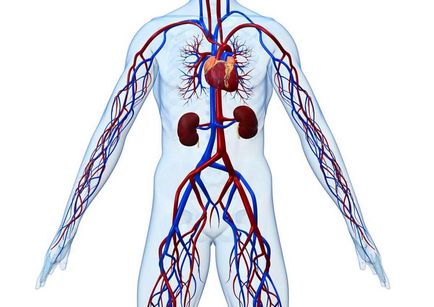

Організм людини - це складна машина, мотором якої є серце. Цей унікальний орган, який працює в «автоматичному» режимі, силою свого викиду штовхає кров до всіх органів і тканин в тілі людини. Насичену киснем артеріальну кров переносять артерії, а по венах до серця повертається вже насичена вуглекислим газів венозна кров. Далі вона знову збагачується киснем, і серцевий цикл повторюється заново. Протягом життя людини такі цикли повторюються мільярди разів, і система працює злагоджено, якщо організм здоровий. Але судини, по яких тече кров, теж можуть хворіти, і одним з найнебезпечніших проявів їх патології є венозний застій.